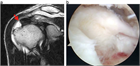

1. 逆に比較的若年男子の外傷性腱板断裂で大きな断裂は、可及的早期(受傷後2カ月以内)の手術が推奨される(推奨度2)